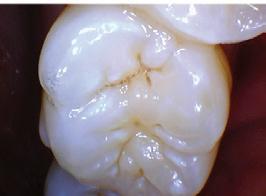

Dental hygienists independently utilize digital scanning for education and motivation. Not only can the clinician educate the patient with the images, but the patient has a visual that is easily understood. These images contain powerful visuals of attrition, fractured teeth, abfraction, gingival recession, overjet, and crowding.4 Biofilm can be displayed after the application of disclosing solution.5 Separate photos are not required to capture the biofilm present when using digital scanning.